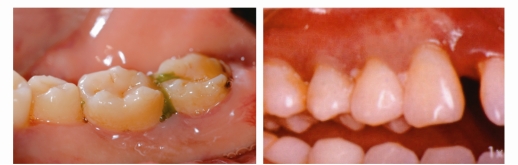

反复的牙龈肿痛溢脓

有些患者牙龈反复“长包”,并且有黄色的脓液流出,这就是牙周炎症导致的“牙周脓肿”。

牙龈萎缩及牙齿敏感

当我们的牙槽骨萎缩时,牙龈会跟着萎缩,牙龈萎缩会导致牙根暴露,继而出现牙齿敏感。